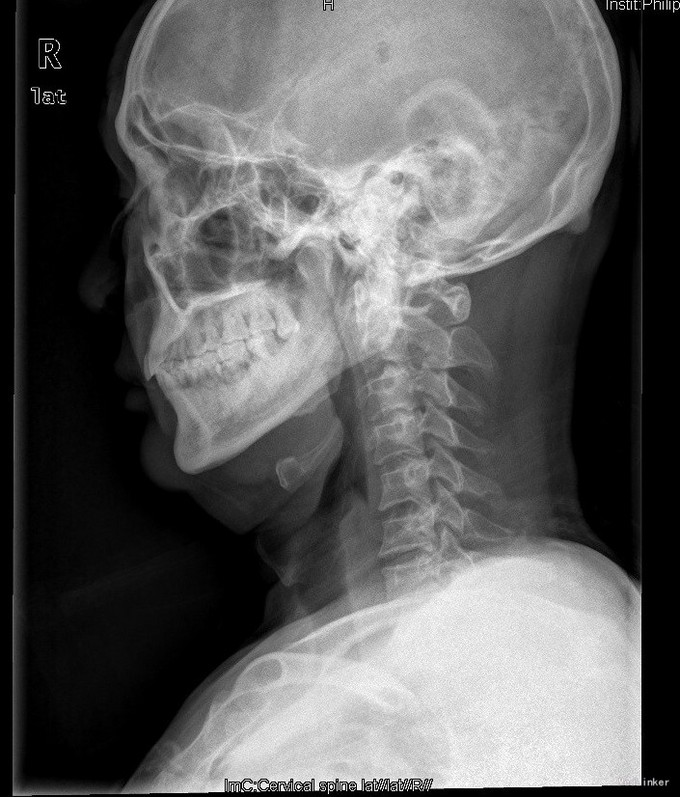

查体:查体:T:36.7oC,P:80次/分,R:20次/分,BP:137/82mmHg。神志清楚,无病容,皮肤巩膜无黄染,全身浅表淋巴结未见肿大。。颈静脉正常。心界正常,心律齐,各瓣膜区未闻及杂音。胸廓未见异常,双肺叩诊呈清音,双肺呼吸音清,未闻及干湿啰音及胸膜摩擦音。腹部外形正常,全腹柔软,无压痛及反跳痛,腹部未触及包块,肝脏肋下未触及,脾脏肋下未触及,双肾未触及。双下肢无水肿。视:平车推入病房,颈椎颈托围领固定,颈部、前额部及全身皮肤未见皮损及异常。触:颈1-4棘突及椎旁明显压痛、叩击痛,感觉正常,四肢肌张力正常。动量:颈椎活动受限,尤以旋转受限为重。双侧肱二头肌反射、肱三头肌反射、膝反射正常,双侧babinski征阴性,右侧Hoffmann征阳性、左侧阴性。 辅助检查:颈椎X线片、MRI、CT提示:寰椎椎板前弓骨折,寰枢关节旋转半脱位

诊断:1.陈旧性寰枢关节旋转脱位2.陈旧性寰椎前弓骨折 治疗:全麻下行:行经前路寰枢椎脱位切开撬拨复位+经后路寰枢椎侧块螺钉内固定、去髂骨后外侧植骨融合术